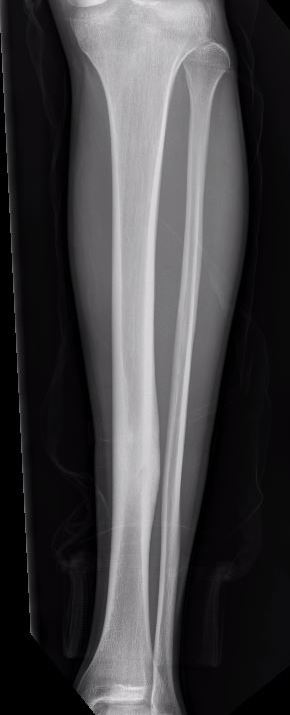

X-ray

Sclerotic bone

Osteoid osteoma tibia